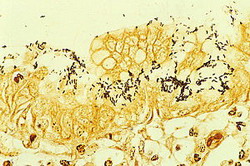

Бактерия была вновь открыта в 1979 году австралийским патологом Робином Уорреном, который затем провёл дальнейшие исследования её вместе с Барри Маршаллом, начиная с 1981 года. Уоррену и Маршаллу удалось выделить и изолировать этот микроорганизм из проб слизистой оболочки желудка человека. Они также были первыми, кому удалось культивировать этот микроорганизм на искусственных питательных средах. В оригинальной публикации Уоррен и Маршалл высказали предположение, что большинство язв желудка и гастритов у человека вызываются инфицированием микроорганизмом Helicobacter pylori, а не стрессом или острой пищей, как предполагалось ранее.